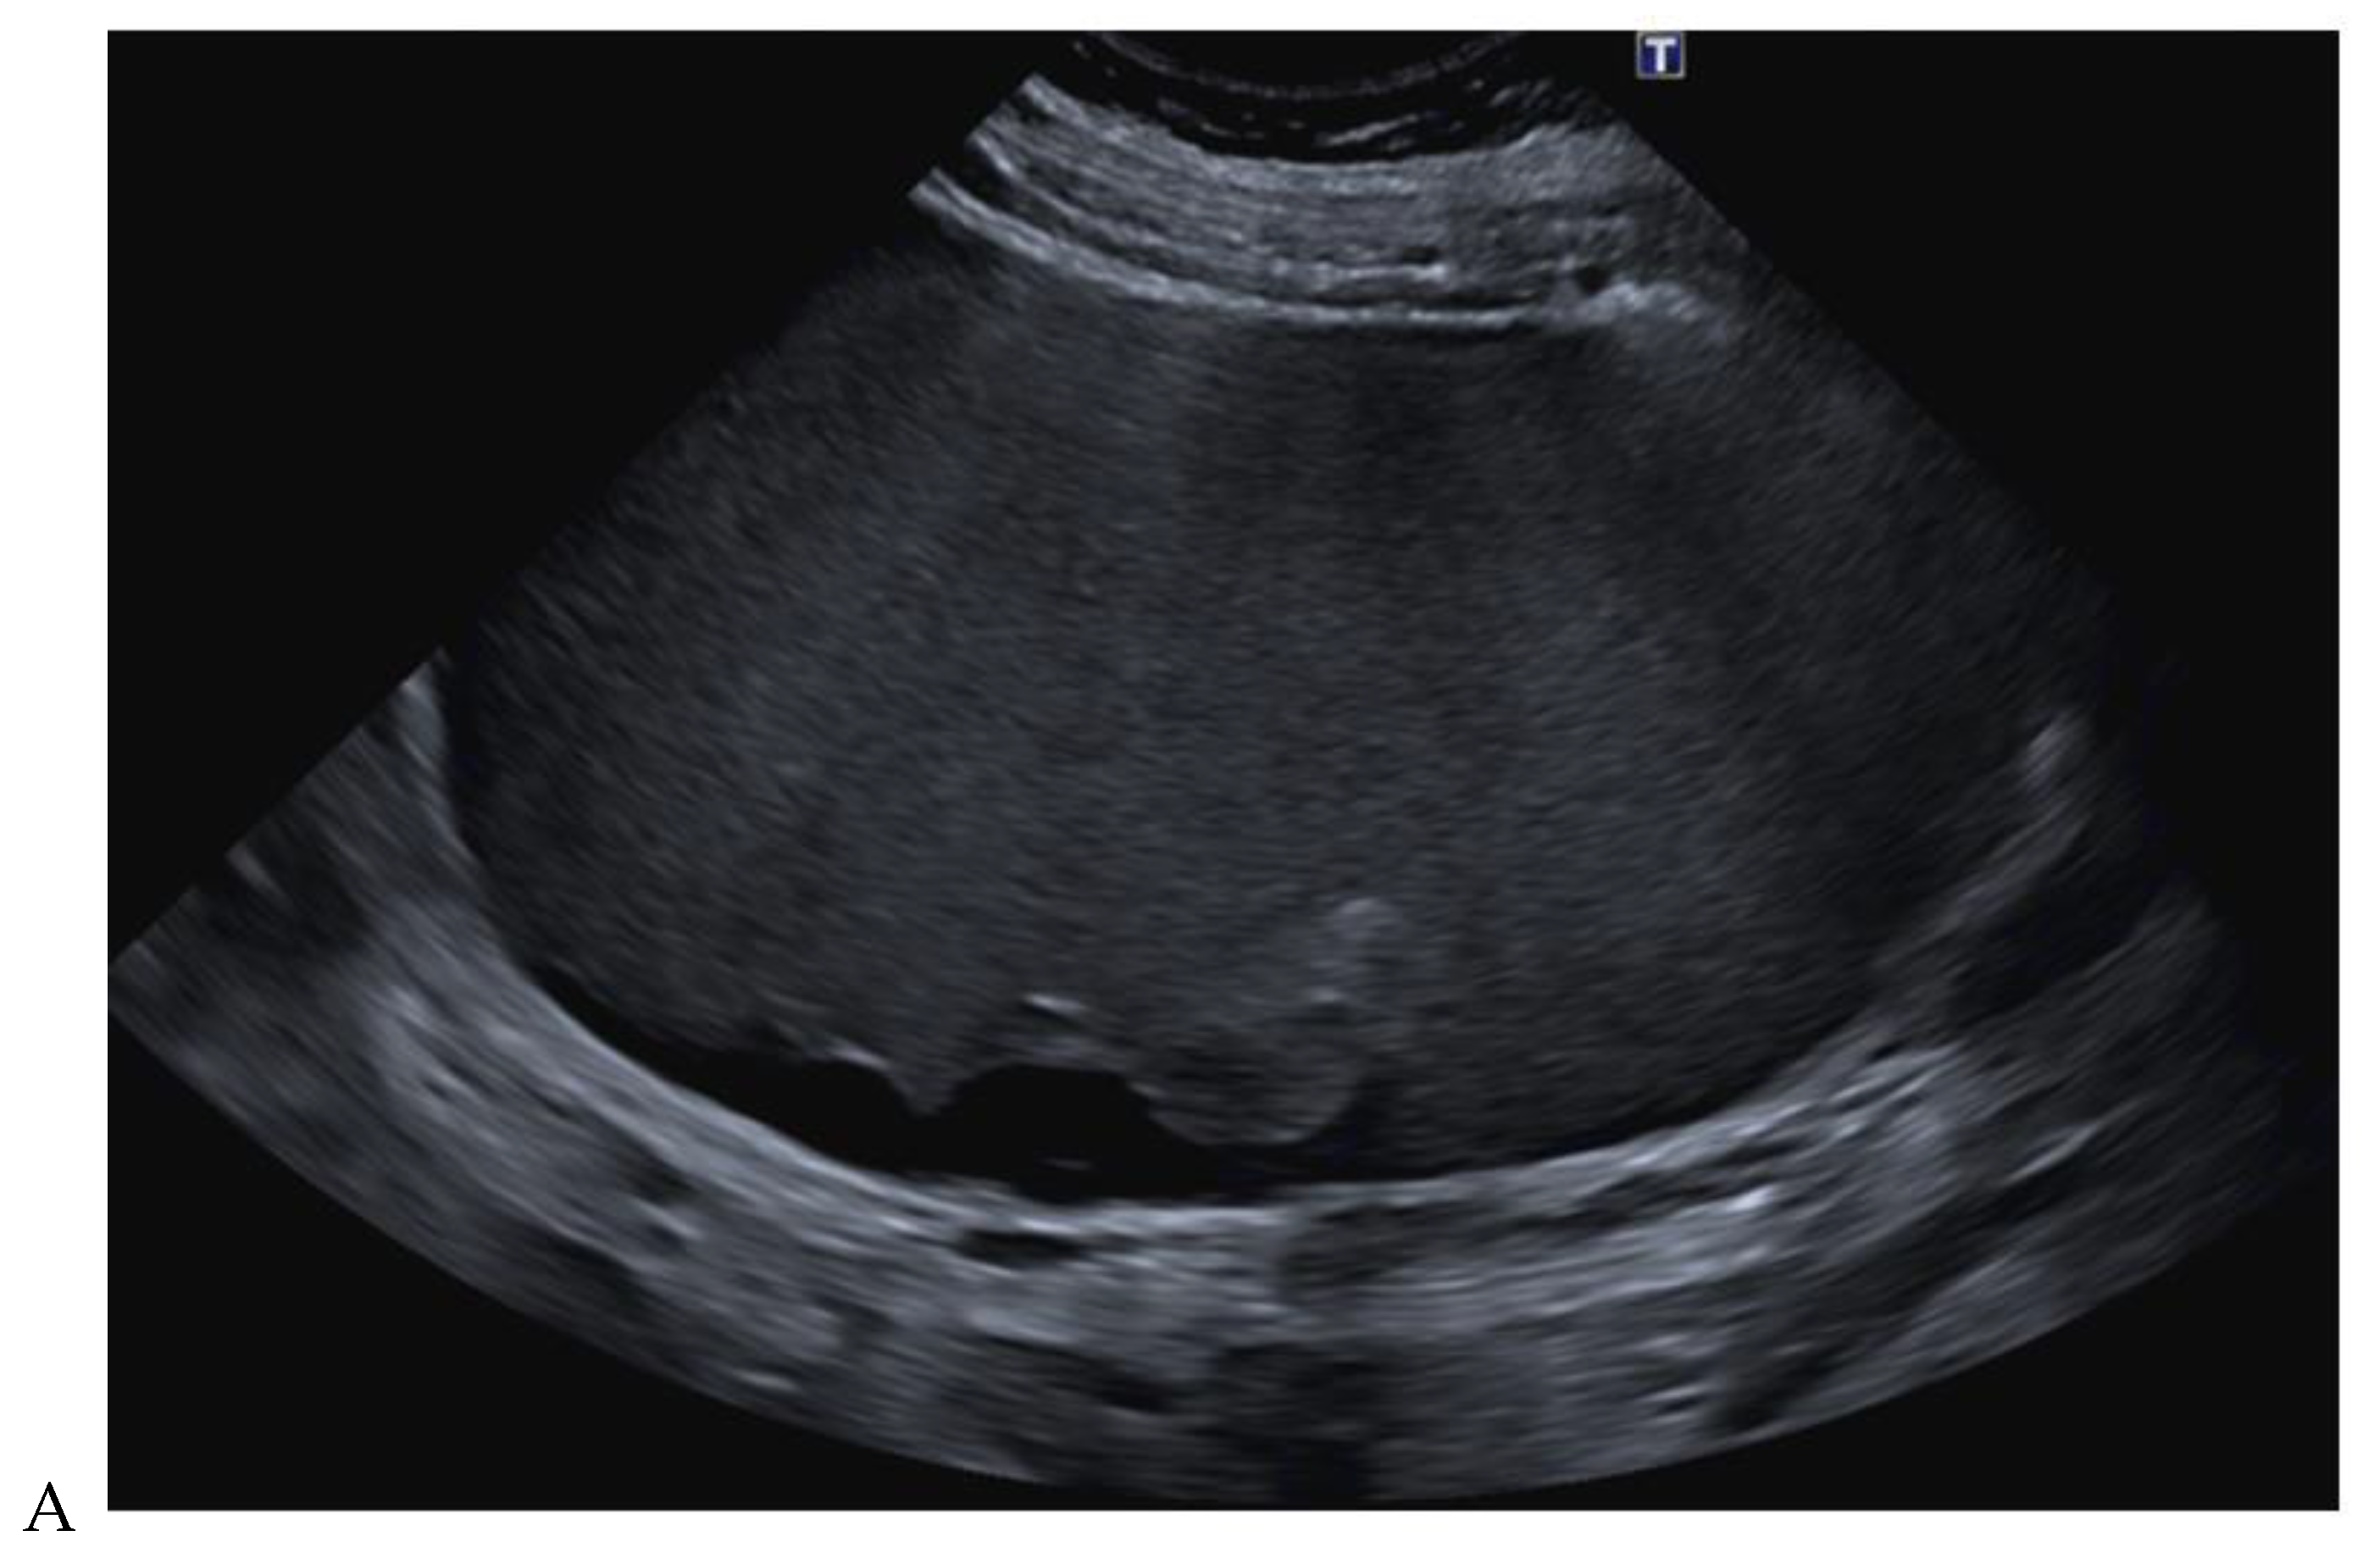

Figure 10.

Papillary renal cell carcinoma in the right kidney of a 54-year-old woman. (A) B-mode ultrasound shows a large right cystic renal mass with heterogeneous contents and a dependent sediment. (B) CEUS with Sonovue® (Bracco Imaging France, Massy, France) reveals the presence of a solid enhancing component at the posterior aspect of the mass. (C) The mass was resected. Pathology identified a necrotic papillary renal cell carcinoma. Courtesy of Pr S. Ferlicot, Department of Pathology, Bicêtre Hospital.